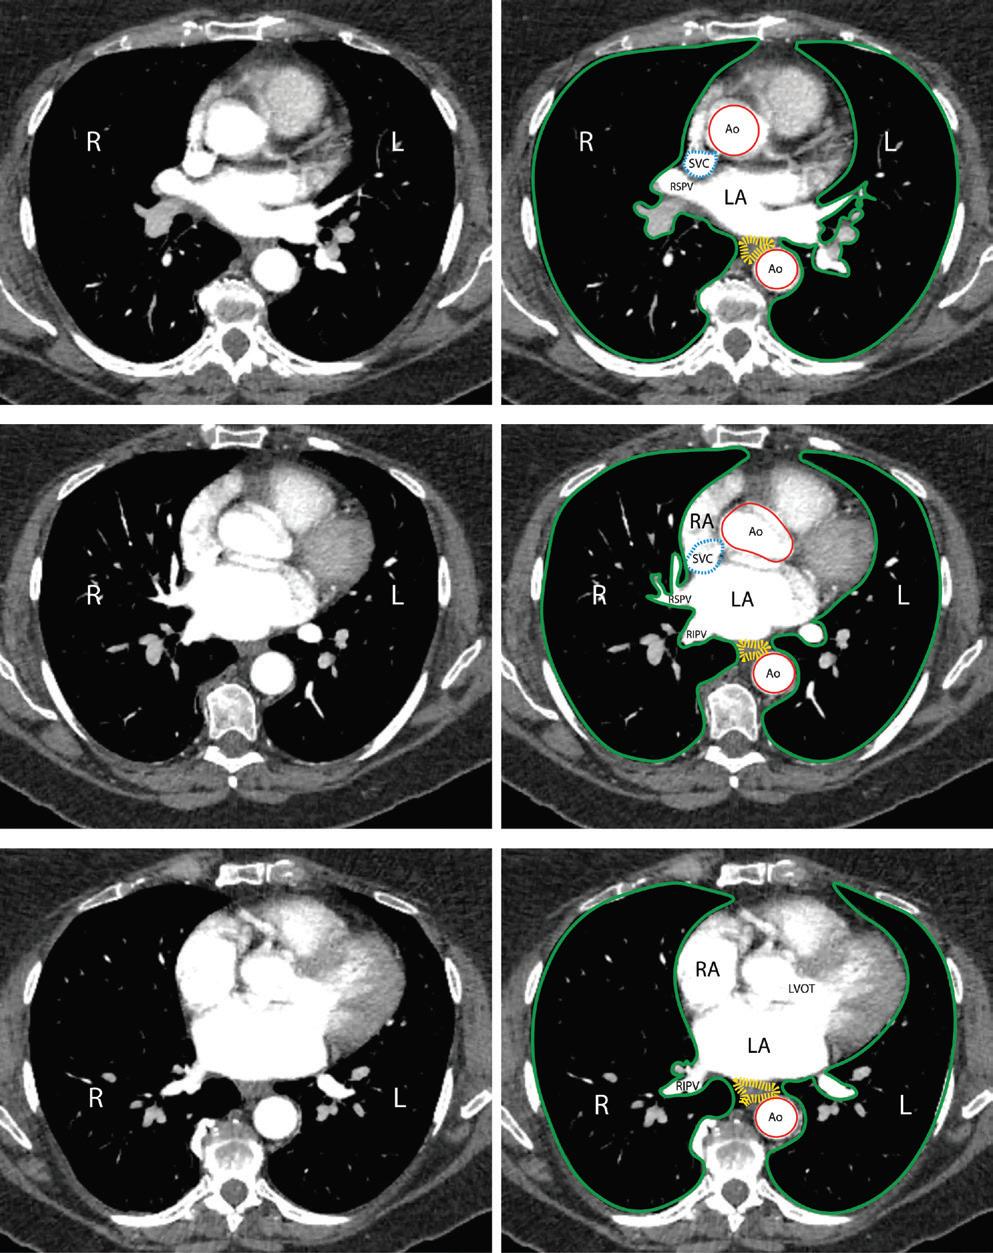

Protecting Against Collateral Damage to Non-cardiac Structures During Endocardial Ablation for Persistent Atrial Fibrillation

Lisa WM Leung, Zaki Akhtar, Jamal Hayat and Mark M Gallagher https://doi.org/10.15420/aer.2021.67